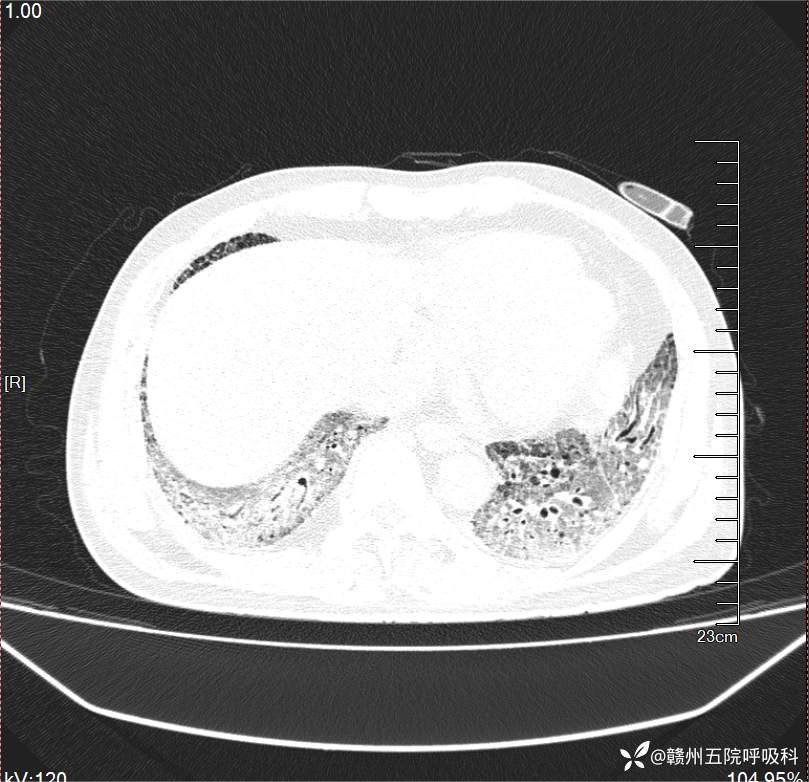

入院后:[常规心电图检查(12导联)]:窦性心律频发房性早搏(部分成对)ST段下移 ;[CT][胸部]:平扫:双肺见多发片状稍高密度影及胸膜下蜂窝影,双肺胸膜下见囊泡透亮影。气管、支气管通畅,未见狭窄或阻塞征,纵隔及双肺门见多发淋巴结显示伴少许钙化影。心影不大,主动脉形态未见异常。双侧胸膜无增厚,胸腔未见积液。增强:双肺病灶无明显强化,所示血管显影清晰,未见充盈缺损。附见肝内少许囊肿。